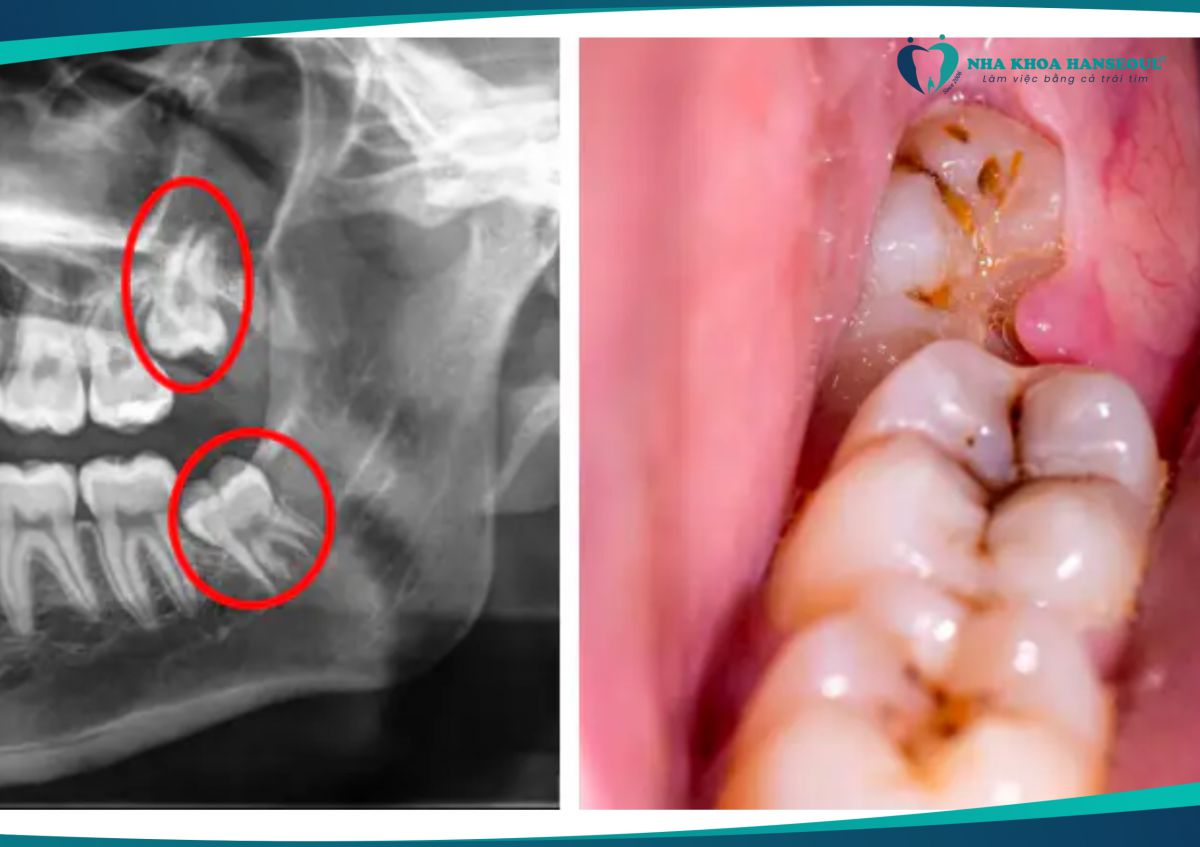

Nếu phim X-quang cho thấy răng số 8 mọc xiên, đâm vào răng số 7 hoặc nằm ngang, nhổ sớm sẽ tránh ảnh hưởng đến răng niềng.

Răng khôn mọc lệch, gây đau nhức nên nhổ bỏ sớm

8 Khám và chụp X-quang đánh giá

- Bác sĩ sẽ kiểm tra, thăm khám và chụp X – quang để đánh giá kích thước, hướng mọc và vị trí răng.

- Đánh giá xem có cần nhổ ngay hay đợi đến giai đoạn nào trong quá trình niềng. Việc này giúp xây dựng phương án nhổ răng số 8 phù hợp và an toàn.